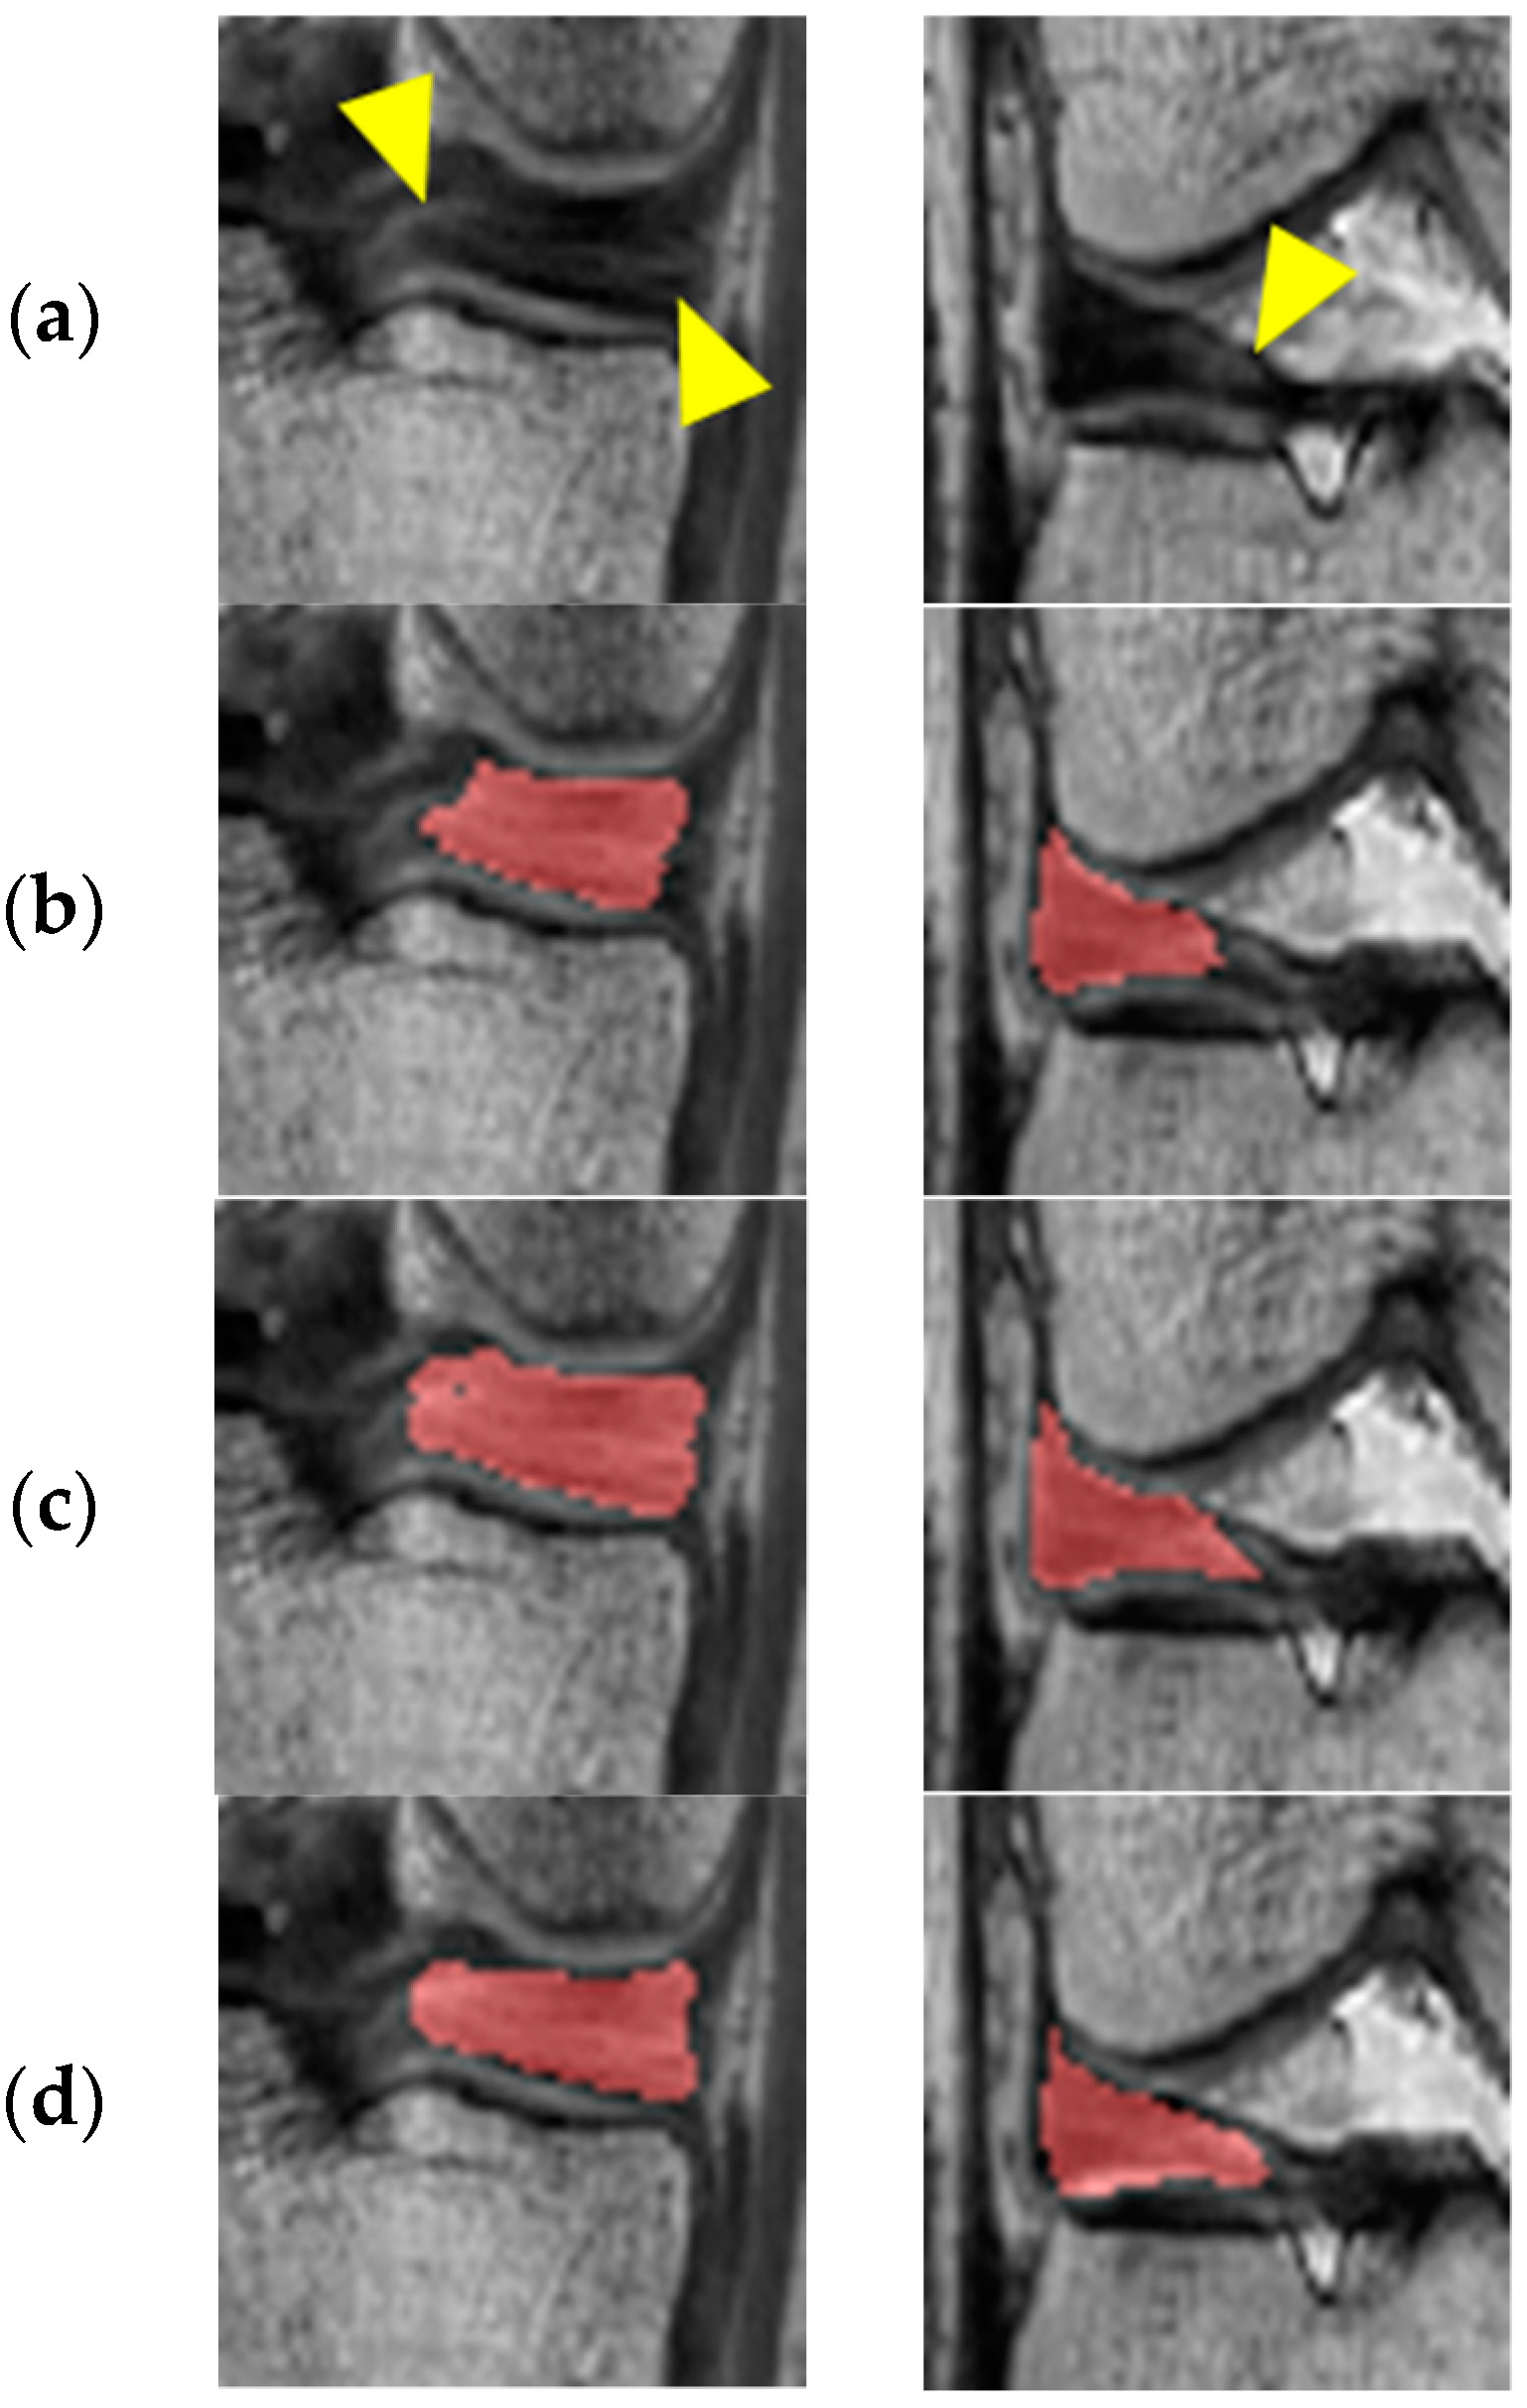

In Figure 5, the first and second columns show the results of adversarial learning for the medial and lateral meniscus, respectively. It can be observed that under-segmentation results due to inhomogeneous intensity levels are prevented through adversarial learning by repeatedly judging and improving the segmentation results.

Figure 5. Segmentation results of before and after adversarial learning: (a) Original image; (b) Before adversarial learning; (c) After adversarial learning; (d) Ground truth.